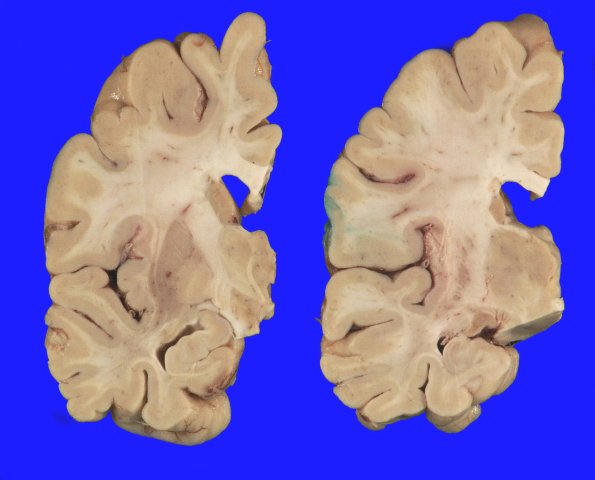

Coronal slicing of the left hemibrain revealed mild dilatation of the lateral ventricle. The hippocampus appeared of normal size.